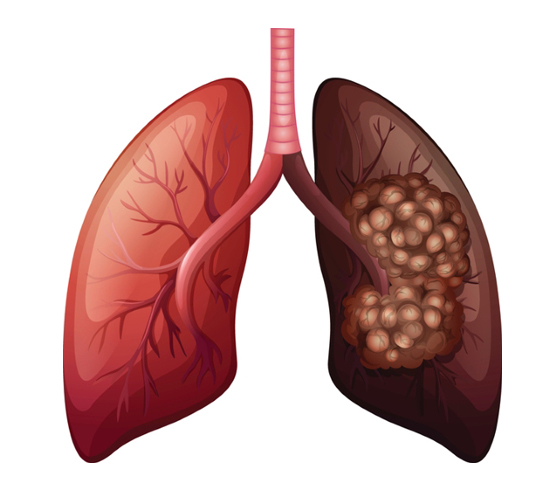

폐암은 폐에 비정상적인 암세포가 증식하여 덩어리를 형성하고 인체에 해를 미치는 것을 말합니다. 즉 폐에 생긴 악성종양을 말하며 폐 자체에 암이 발생하거나 다른 장기에서 생긴 암이 폐로 전이되어 발생합니다.

폐암 발병률과 폐암 사망률은 지속적으로 증가하고 있으며 폐암 진단을 받고 5년 이내 사망률은 86%나 된다고 합니다. 폐암은 재발이나 전이가 많고 완치율이 낮은 암입니다. 다른 암에 비해 사망률이 높습니다.